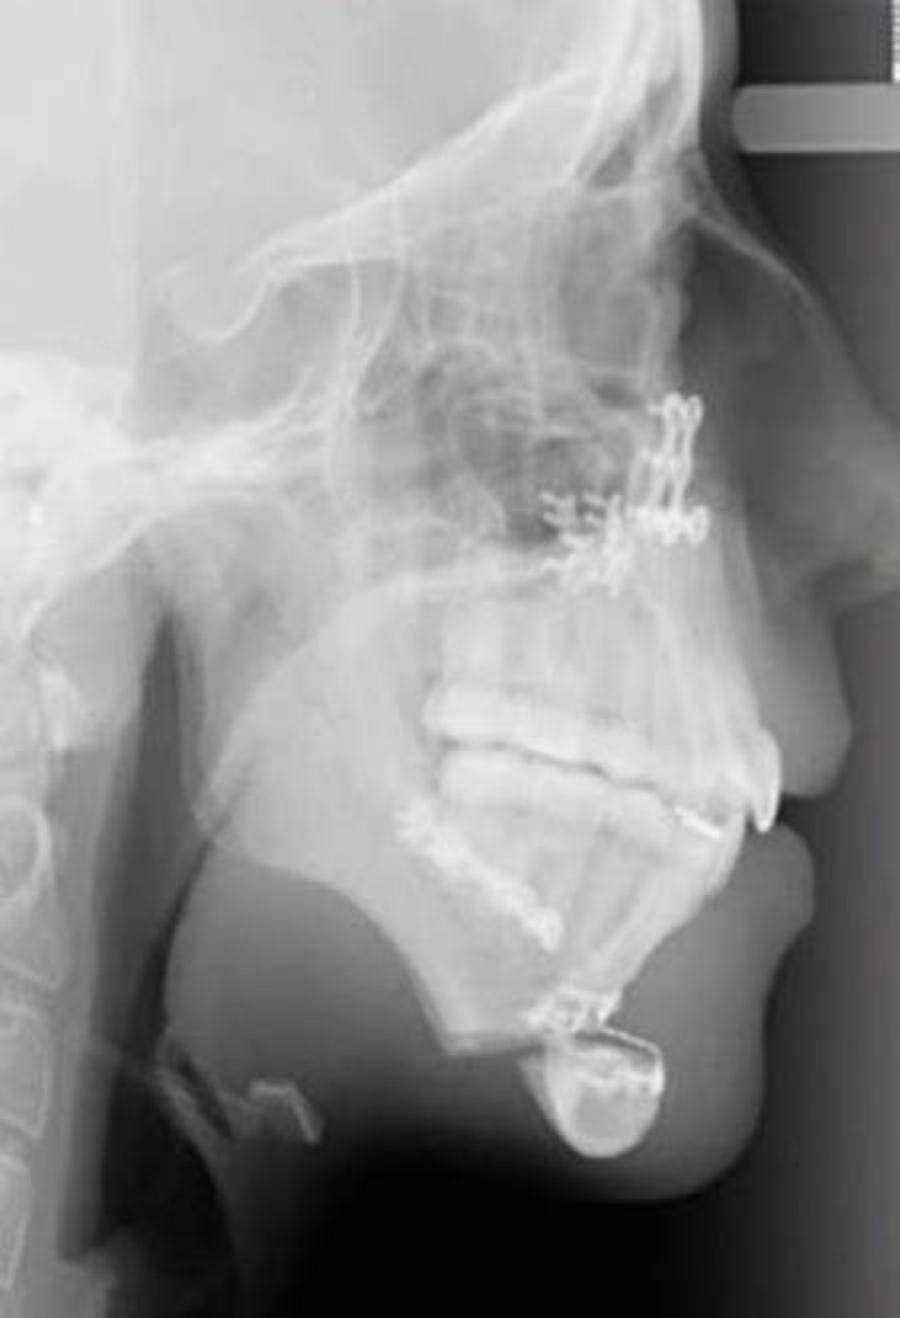

Η οικογένεια επισκέφθηκε έναν γναθοχειρουργό, ο οποίος βοήθησε στη μεταμόρφωση της Ellie Jones. Το πρώτη χειρουργείο προκάλεσε πολύ πόνο στην 20χρονη. Ήταν ιδιαίτερα δύσκολο σαν χειρουργείο και στο τέλος του έπρεπε να κάνει σωστή διατροφή. Αυτή εμπεριείχε μόνο υγρά για χρονικό διάστημα ενός μηνός, ενώ στο ξεκίνημα δεν μπορούσε να μιλήσει.

Στο χειρουργείο, που ακολούθησε, το οποίο ήταν δεύτερο κατά σειρά μπόρεσε να διορθώσει το πηγούνι της. Έτσι, μπόρεσε να μεταμορφωθεί και να φτιάξει παράλληλα και την ψυχολογία της.